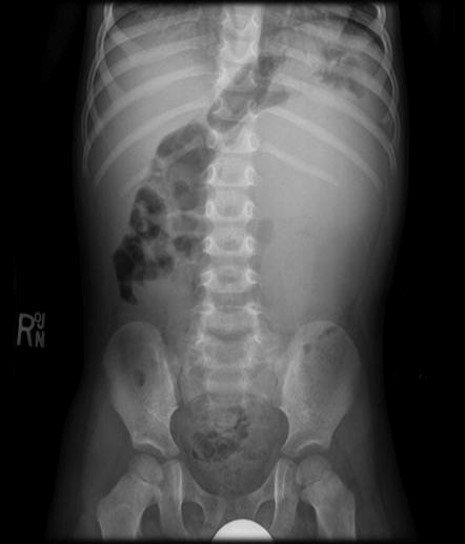

NESTA RADIOGRAFIA SIMPLES DO ABDOME, VC OBSERVA UM VELAMENTO DIFUSO DO HEMIABDOME ESQUERDO, COM EFEITO COMPRESSIVO NAS ALÇAS INTESTINAIS PREENCHIDAS POR GASES , QUE SE ENCONTRAM DESLOCADAS .

TUMOR MALIGNO MAIS FREQUENTE NA INFÂNCIA.ASSINTOMÁTICO ATÉ QUE A MÃE PERCEBE A MASSA ABDOMINAL.

A patologia renal mais comum em criança com massa palpável é?

Tumor de Wilms